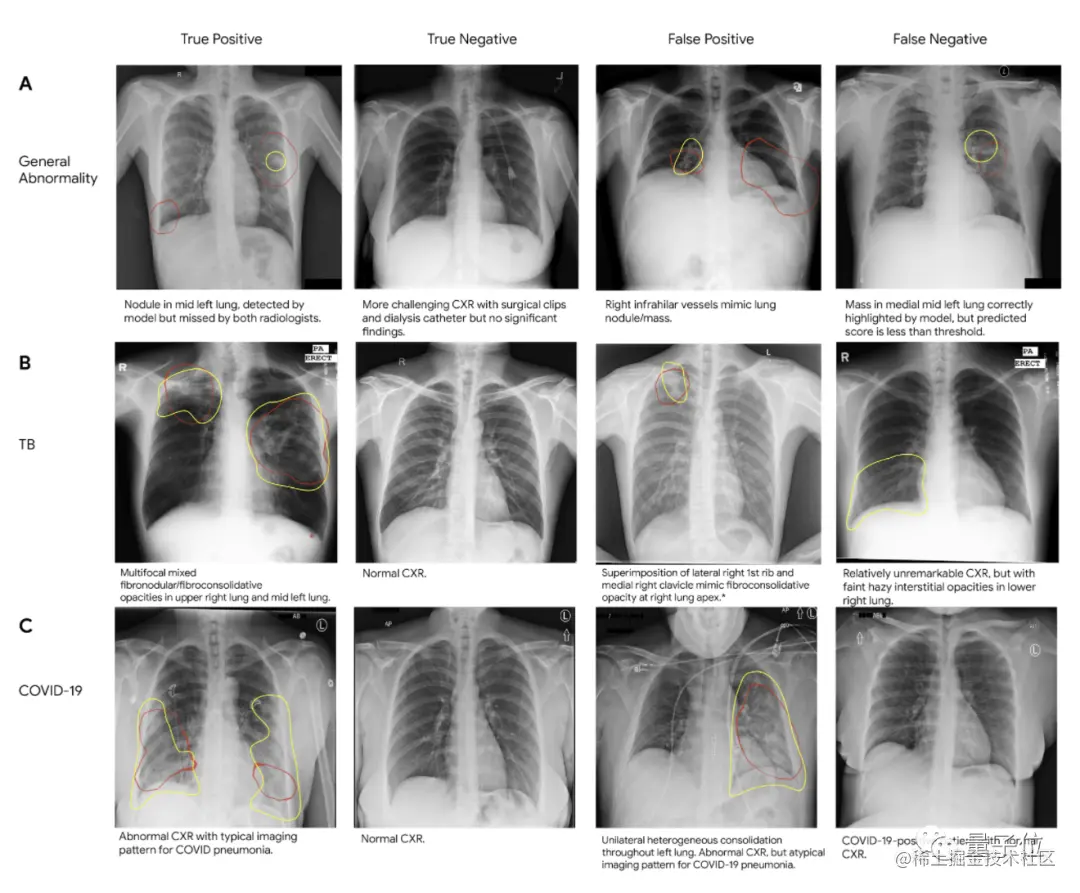

Jeff Dean还强调在疾病诊断,尤其是在医学成像上的应用,比如在改善乳腺癌筛检、检测肺癌、加速癌症的放射治疗、标记异常X射线和前列腺癌期活检等领域。

图片